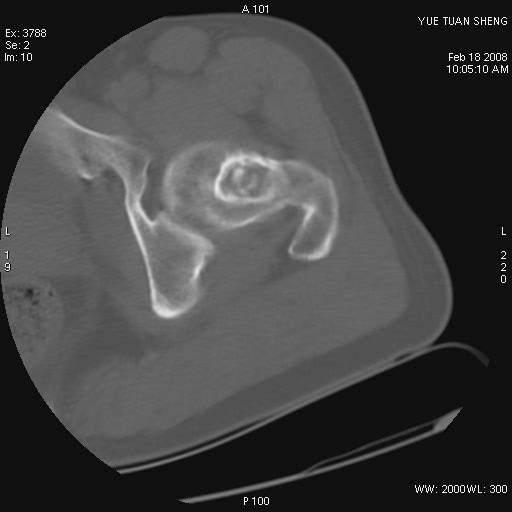

患者,男,56岁,左髋部疼痛1个月,x线:左股骨头高密度影,性质待定,右侧正常。左髋ct如图

左股骨颈区椭圆形磨玻璃样影,边缘明显硬化环环绕,其内见斑点状类钙化高密度影考虑 良性骨病-----骨纤,骨化性纤维瘤,内生软骨瘤。